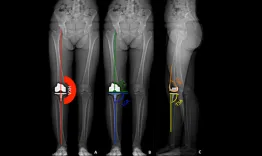

Adding an extra-articular gesture to an ACL reconstruction is getting more and more used. This presentation explains why, and the different ways to do it with several surgical techniques.

Strategy for anterolateral stabilization

Etienne Cavaignac